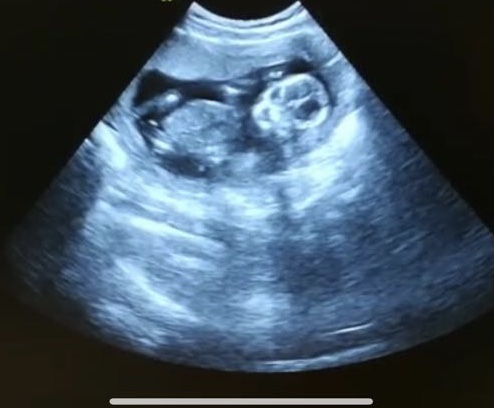

Hi! I think the little bright white stripe between the legs are boy goods.. what do you all think? Attachment 40234

Ehh, I wouldn't go by that. What gestation? It could also be cord. (For what it's worth, I have a shot like this too, and we don't know gender yet, but it's very easily something not nub).